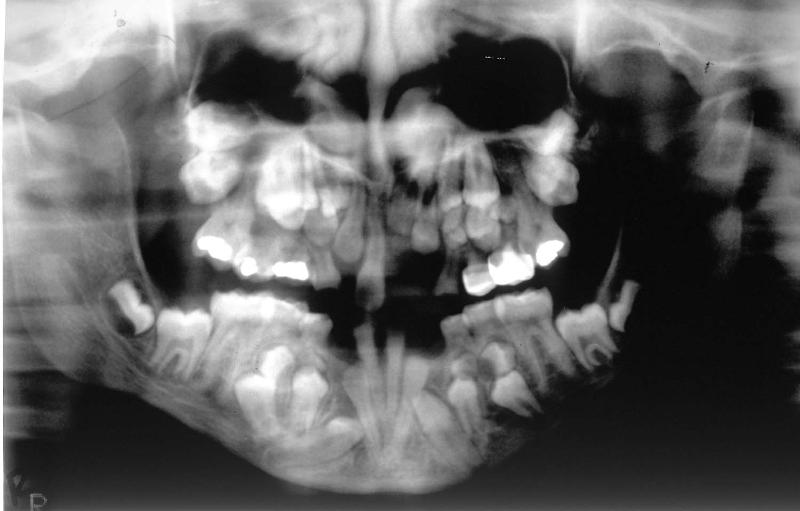

The panoramic radiograph above illustrates a case of a congenitally missing permanent maxillary right lateral incisor. The permanent mandibular right third molar had been previously extracted (courtesy of Dr. BM Cleghorn, Dalhousie University).

|

The bitewing radiograph on the left is of the patient's posterior right and illustrates the posterior teeth in quadrants 1 and 4. The primary maxillary right second molar is retained and the permanent maxillary right second premolar is congenitally missing (courtesy of Dr. BM Cleghorn, Dalhousie University).